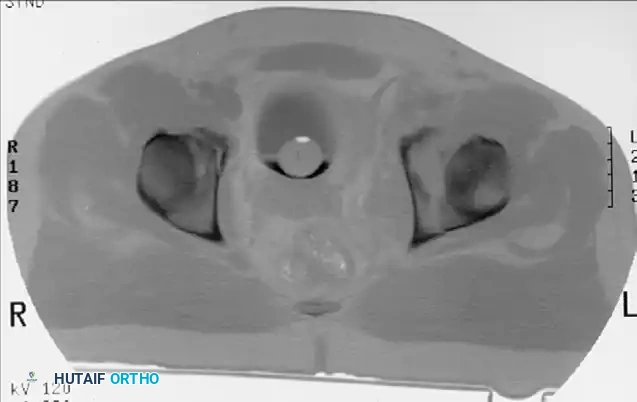

Incarcerated Intra-Articular Fragments

Following the closed reduction of a hip dislocation, a post-reduction CT scan is mandatory. While small avulsions of the ligamentum teres sequestered deep in the cotyloid fossa may be observed, any osteochondral fragment lodged between the articulating surfaces of the femoral head and the acetabular dome necessitates urgent surgical excision and joint irrigation.